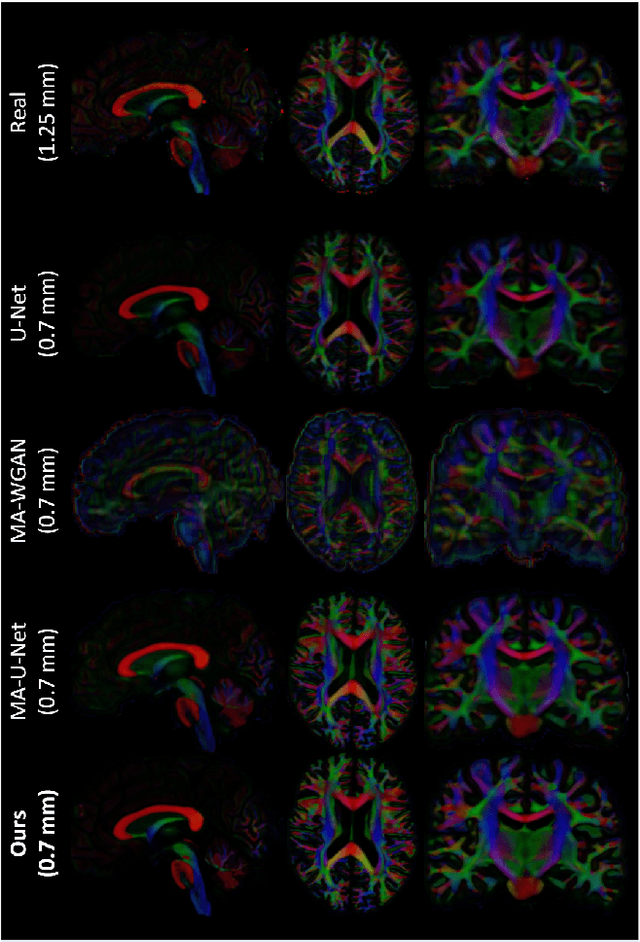

Abstract:Unpaired image-to-image translation has been applied successfully to natural images but has received very little attention for manifold-valued data such as in diffusion tensor imaging (DTI). The non-Euclidean nature of DTI prevents current generative adversarial networks (GANs) from generating plausible images and has mostly limited their application to diffusion MRI scalar maps, such as fractional anisotropy (FA) or mean diffusivity (MD). Even if these scalar maps are clinically useful, they mostly ignore fiber orientations and have, therefore, limited applications for analyzing brain fibers, for instance, impairing fiber tractography. Here, we propose a manifold-aware CycleGAN that learns the generation of high resolution DTI from unpaired T1w images. We formulate the objective as a Wasserstein distance minimization problem of data distributions on a Riemannian manifold of symmetric positive definite 3x3 matrices SPD(3), using adversarial and cycle-consistency losses. To ensure that the generated diffusion tensors lie on the SPD(3) manifold, we exploit the theoretical properties of the exponential and logarithm maps. We demonstrate that, unlike standard GANs, our method is able to generate realistic high resolution DTI that can be used to compute diffusion-based metrics and run fiber tractography algorithms. To evaluate our model's performance, we compute the cosine similarity between the generated tensors principal orientation and their ground truth orientation and the mean squared error (MSE) of their derived FA values. We demonstrate that our method produces up to 8 times better FA MSE than a standard CycleGAN and 30% better cosine similarity than a manifold-aware Wasserstein GAN while synthesizing sharp high resolution DTI.